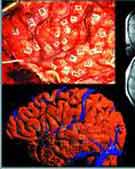

人脑图集通过国际互联网向所有注册用户免费开放。图集由大脑三维图像组成,它描绘了大脑活动,详细标注出负责语言、记忆、情感的各个功能区域。人类的大脑千差万别,没有两个人的大脑是完全相同的,即使同卵双胞胎的大脑也不相同。医生面对大脑时,凭什么判断它是否正常?科学家现在正努力理解“正常”大脑的标准究竟是什么?为此他们想到了绘制人类大脑图谱。

人脑图集通过国际互联网向所有注册用户免费开放。图集由大脑三维图像组成,它描绘了大脑活动,详细标注出负责语言、记忆、情感的各个功能区域,并强调个体之间和特定群体之间在具体区域的差异。

所有的大脑图像都经过伸展、收缩等处理,以达到统一参考标准,方便研究者做一一对应的比较。美国国家医学图书馆的迈克尔·J·阿克曼说,人脑图集所展现的“大图像”的清晰度是个别的脑扫描图像所无法企及的。“这就好比从一块拼图无法发现整体的美一样。”阿克曼是“可见人类计划”(Visible Human Project)的倡导者之一,可见人类计划是将人体各个部分的三维图像编汇成数字图集。